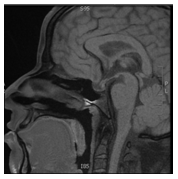

A 31years old man presented to the emergency department with five days history of severe headache accompanied by nausea, dizziness, and blurred vision. The patient’s past medical history was unremarkable and was not on any medications. He is married with 3children, the youngest is 3years old. On physical exam, he was hemodynamically stable with no orthostasis, conscious, oriented and in moderate pain distress (5/10 on pain scale chart). His central nervous system exam showed normal mini-mental status, cranial nerves examination was normal with preserved visual fields. His presentation prompted a brain MRI which showed pituitary macroadenoma with a suprasellar extension (Figure 1) with hemorrhage suggestive of pituitary apoplexy. Hormonal profiles is shown in Table 1, consistent with panhypopituitarism due to non-functional pituitary macro-adenoma with apoplexy. The decision for conservative management was opted for in keeping with the severity of the presentation. He improved and discharged 2days later on hydrocortisone and levothyroxine. However, a few days later he expressed a major concern of diminished libido and sexual dysfunction. At this point, Cabergoline 0.5mg orally twice weekly (off-label) was started with an improvement in his sexual functions within a few days, recovering his pituitary functions (off hormonal replacement). Follow-up MRIs (Figure 2) showed marked shrinkage of the macroadenoma which completely resolved in the most recent image (Figure 3) two years later.

Figure 1 Pituitary macroadenoma with a suprasellar extension